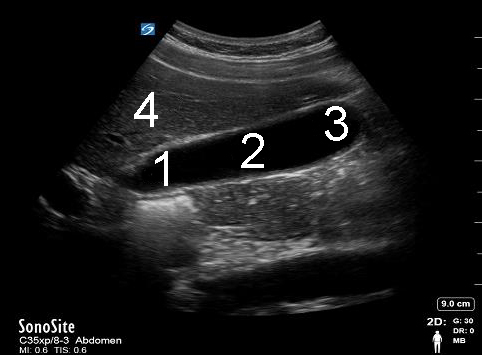

胆嚢矢状画像

頸部

身体

眼底

肝臓